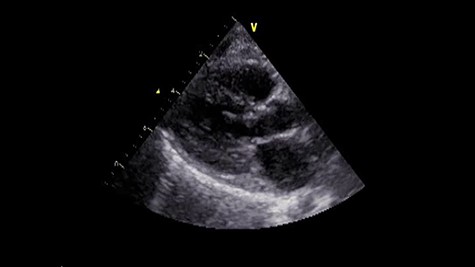

A male infant born at 34-week gestation with 1531-g birth weight was diagnosed with porencephaly based on fetal examination. The patient had persistent hemolytic anemia and jaundice and was diagnosed with a mutation in collagen type IV alpha 1 chain (COL4A1) by postnatal genetic analysis. The details of metabolic and muscular complications of the patient were described in a previous report [2]. The patient underwent surgery for ventriculoperitoneal shunt placement for hydrocephalus and seizure at the age of 3 months and was hospitalized several times for recurrent pneumonia until the age of 2 years, at which time he was diagnosed with LVOTS and moderate MR. The patient was treated with β-blockers for 6 months, but LVOTS and MR gradually worsened and SAM of mitral valve was detected at the age of 2 years and 8 months. At the time, the peak pressure gradient of left ventricular outflow tract (LVOT) was 120 mmHg and the MR was severe (Fig. 1 and Video 1). Surgery was planned for septal myectomy for LVOT with mitral valve repair.

Preoperative echocardiography. The abnormal muscle band in left ventricle and severe SAM of the mitral valve are observed. The anterior leaflet of mitral valve obstructs the LVOT in the systolic phase.